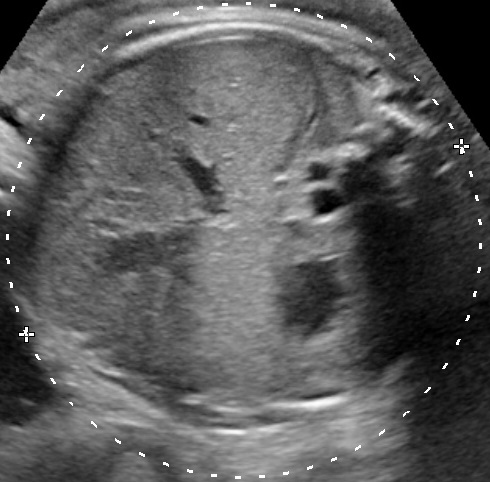

The interrupted inferior vena cava (IVC) with azygos continuation to the superior vena cava (SVC) arises from a failure to form the right subcardinal–hepatic anastomosis, resulting in absence of the hepatic segment of the IVC. This anomaly characterizes left atrial isomerism (Polysplenia) which is commonly associated with atrioventricular septal defect and complete heart block. The sonographic landmark is a dilated azygos vein alongside the aorta on the abdominal circumference plane and four-chamber view plane (Yagel S., et al., 2010).

Interrupted IVC with azygos continuation to the SVC has also been reported as an isolated entity, in which cases it is usually clinically silent. Our featured case shows an isolated interrupted IVS with azygos continuation to the SVC.

Interestingly, the ratio of the diameters of Azygos/Descending Aorta at the height of the four-chamber view is constant during pregnancy and it may be used as a useful maker for prenatal screening and diagnosing of interrupted inferior vena cava. The median of AZ/DAO ratio in normal group and IIVC group were 0.38 (ranged from 0.24–0.62) and 0.70 (ranged from 0.64–0.78), respectively (Xie H. and Wu, L., 2014).